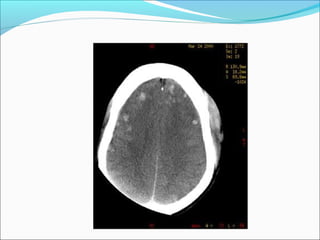

SUBDURAL HEMATOMA

Radiological signs

ļ‚—Crescent shape

ļ‚—The most common locations are the frontal and

parietal convexities.

ļ‚—Countercoup

ļ‚—Unlike an EDH, its spread is not limited by suture

lines; it can spread over the whole convexity, but it

almost never crosses the midline

ļ‚—Mass effect +/-brain herniation

ļ‚—Skull fracture in < 50 %

MANAGEMENT OF SDH

ļ‚—Acute SDH with thickness > 10 mm or midline shift >

5mm should be evacuated

ļ‚—Patient in coma with a decrease in GCS by >2 points

with a SDH should undergo surgical evacuation.